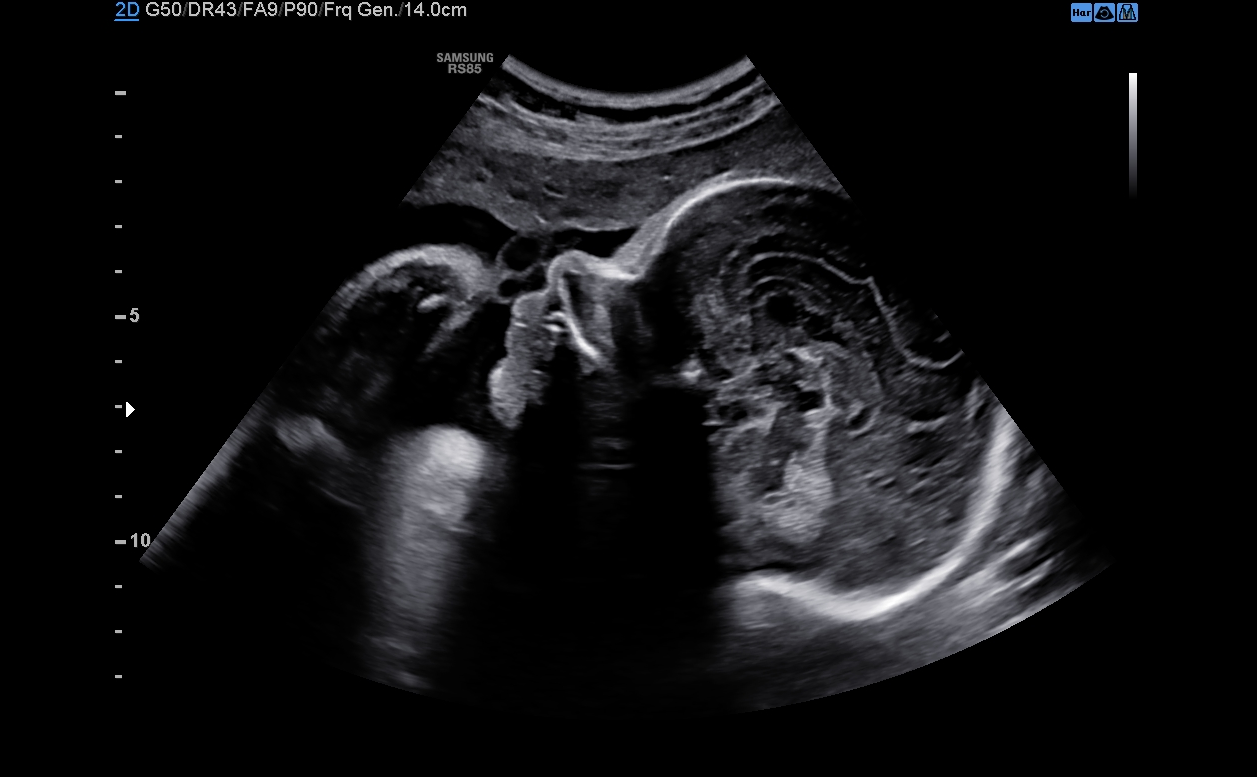

Filtr pro redukci šumu zlepšuje kvalitu 2D obrazu

Optimální diagnostický výkon zajišťuje filtr redukce šumu, který zajišťuje zvýraznění hran a vytváří ostřejší 2D obraz. O výrazné zlepšení kvality zobrazení se starají specializované technologie Samsung. ClearVison navíc poskytuje optimalizaci pro konkrétní aplikaci a pokročilé časové rozlišení v režimu živého skenování.